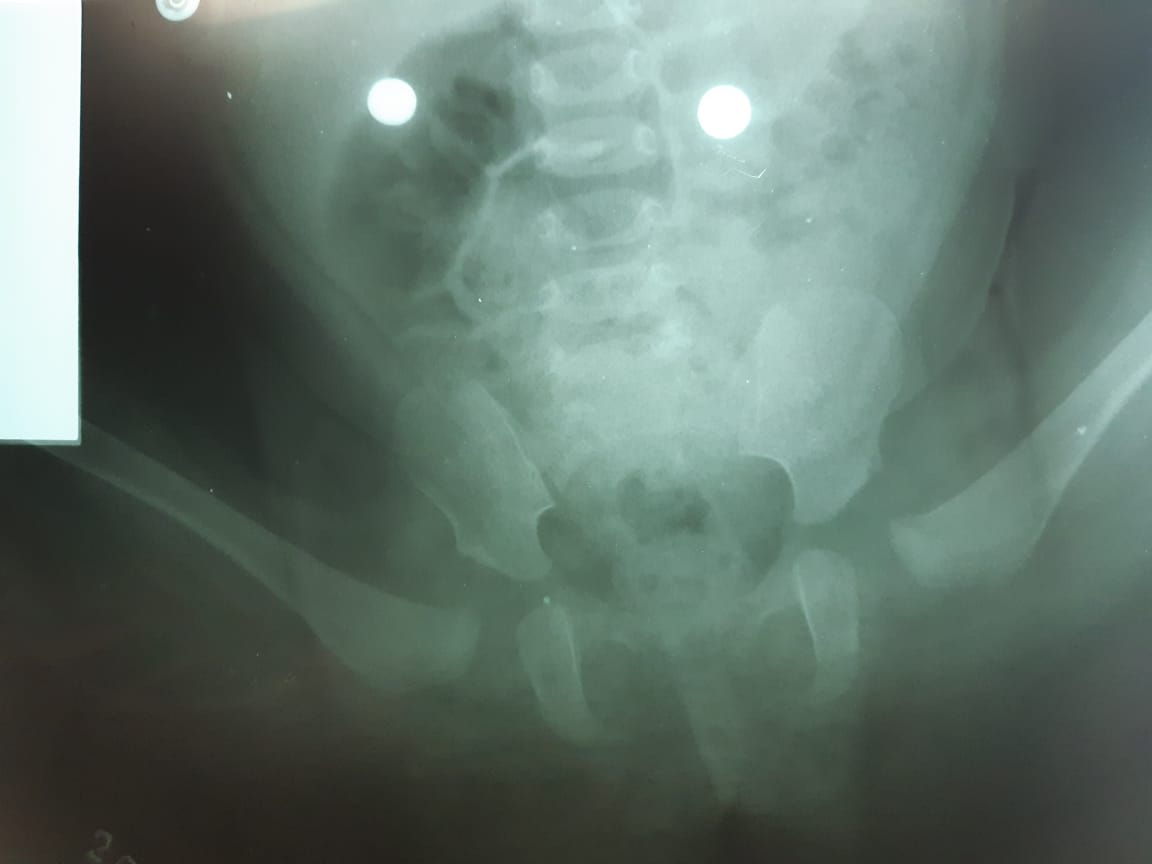

Arnés corrige la luxación de cadera.

La luxación parcial o total de cadera es un trastorno congénito conocido como displasia de cadera. El bebé que la tiene no siente ningún dolor, la cadera fuera de su lugar no le produce molestia alguna, tampoco le impide mover las piernas con normalidad.

El doctor Pinto indicó que la cadera es colocada en su lugar de manera manual y para mantenerla ahí se instala el arnés de Pavlik. Este es un dispositivo que permite que la cadera quede asegurada en su lugar y brinda comodidad al bebé al conservar el libre movimiento de las piernas. El tiempo promedio de uso es de tres meses durante todo el día.

Desde que el especialista coloca el arnés, solo él puede retirarlo al constatar que la cadera quedó definitivamente en el lugar correcto. El médico, de ser necesario, ordena estudios puntuales para verificar el éxito del tratamiento.